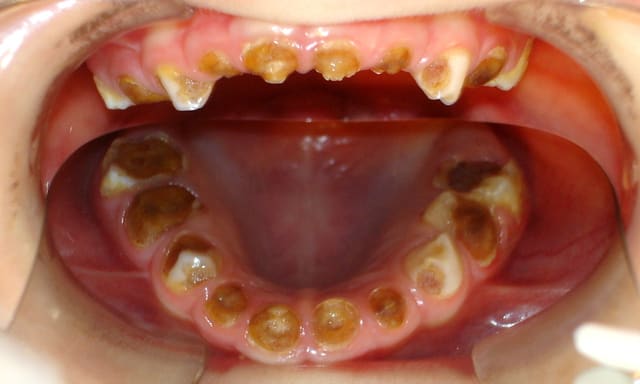

- Voici la pano de départ : oui, des pulpec et CPP auraient pu être été indiquées, dans l'idéal. Mais au vu du contexte (polycaries à 80%, mauvaise hygiène locale et alimentaire) et du fait que les listes d'attente pour les soins sous AG sont déjà très longues, une solution plus "sûre" a été choisie.

- Oui, il y a une déviation du milieu incisif prothétique maxillaire, c'est bien moche, dommage. J'ai l'impression sur la photo en dessous qu'il a peut être une latéro-déviation mandibulaire gauche.